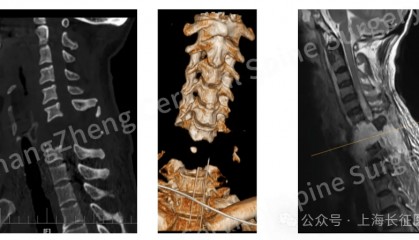

全球罕见!中国医生救回“身首离断”患者

从业近30年,上海长征医院颈椎外科病区主任陈华江教授接诊过无数凶险的颈椎外伤患者,但称得上是“身首离...

bitop交易所官方网 2025-08-18 21